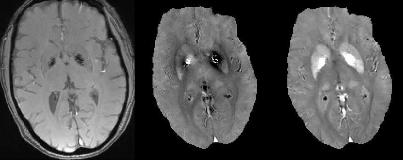

QSM은 T2* 강조 영상에서 구별이 어려운 석회화와 철 침착을 구분하는 데 도움을 줄 수 있다.[19] 피질 뼈의 주요 구성 요소인 석회화는 생체 내 및 팬텀 실험에서 물과 비교했을 때 반자성체로 확인되었다.[11][18] 따라서 QSM을 통해 강한 상자성체를 띄는 철 침착물과 석회화를 구별할 수 있다.

4. 1. 석회화와 철의 구별

QSM은 석회화와 철 침착을 구별하는 데 유용하며, T2* 강조 영상에서 혼동될 수 있는 저신호 강도 소견의 진단에 도움을 줄 수 있다.[19] 주요 구성 요소가 석회화인 피질 뼈는 물과 비교하여 생체 내 및 팬텀 실험에서 반자성체로 확인되었다.[11][18] 따라서 이 반자성을 사용하여 강한 상자성체를 나타내는 철 침착물과 석회화를 구별할 수 있다.4. 2. 조영제 정량화